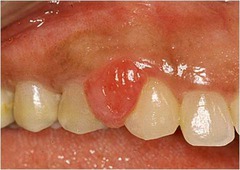

"pregnancy tumor" a)gingival hyperplasia b)papillary hyperplasia of the palate c)epulis fissuratum d)pyogenic granuloma

Front

pyogenic granuloma- granulation tissue in response to local irritant

Back